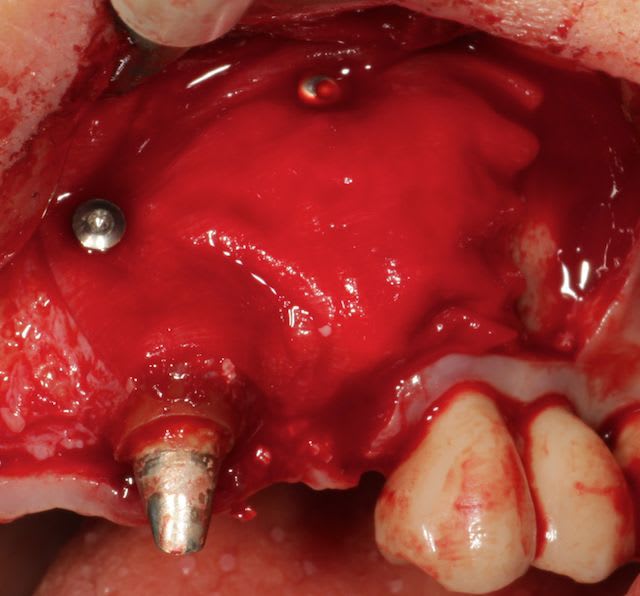

Grosse perte osseuse au niveau de la 23, ROG avec Bio-Oss et autogène dans un rapport 50/50, le tout recouvert pas une BIo-gide maintenu avec de pin's.

Désolé pour le retard, je vais essayé de répondre à tout le monde, mettre un implant et faire une ROG de façon predictible dans un cas comme ça c'est impossible, la photo pré-op c'est la dernière ( je ne sais pas pourquoi nonol m'a inversé l'ordre ), à noter que j'ai fait ce design d'incision car 24 et 25 sont des implants et je ne voulais justement pas me retrouver avec une récession.

J'ai utilisé du BIo-Oss et de l'autogène prélevé avec un scraper à la mandibule, le tout recouvert par une Bio-Gide maintenu par des pin's, suture avec du Gore Tex ( e-PTFE ) et du Cytoplast (PTFE )